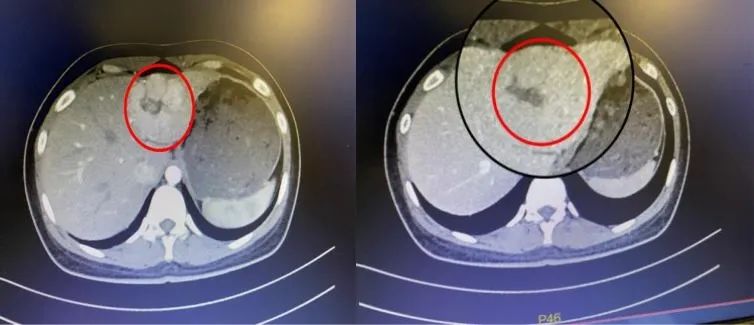

23 岁未婚的陈女士(化名),在外院进行体检时发现肝左叶实质性占位,建议手术治疗,由于工作繁重和生活琐碎,并没有马上进行治疗处理。直至近期,复查发现肿物有所增大。便慕名来到了漳州第三医院普外一科周智主任门诊就诊,在进一步的检查中发现,陈女士的肝左外叶有 6 公分多的占位,性质不明,建议入院接受手术治疗。

经过与陈女士的沟通后,了解到陈女士未婚,对手术伤口外观有一定的美观诉求,周智主任团队全面评估患者的病情后,经过详细术前论证,认为可为其实施创伤更小、切口更少的单孔腹腔镜手术。